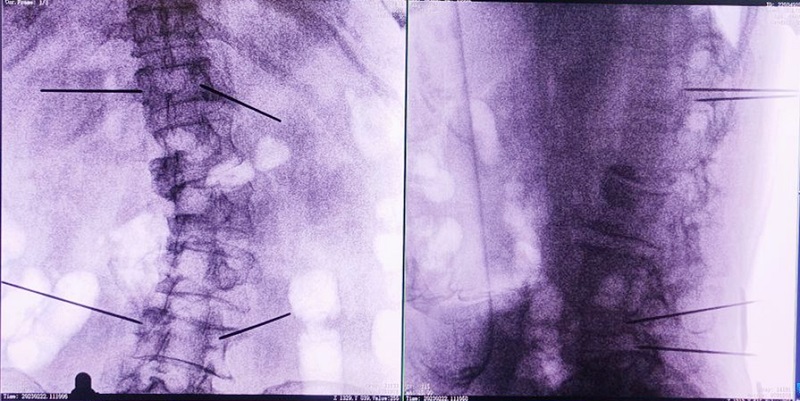

(3)根據(jù)設(shè)定好的的位置和入針方向,植入引導(dǎo)針;

(4)所有引導(dǎo)針植入完畢后,沿引導(dǎo)針方向進行椎弓根及椎體置管,建立通道;